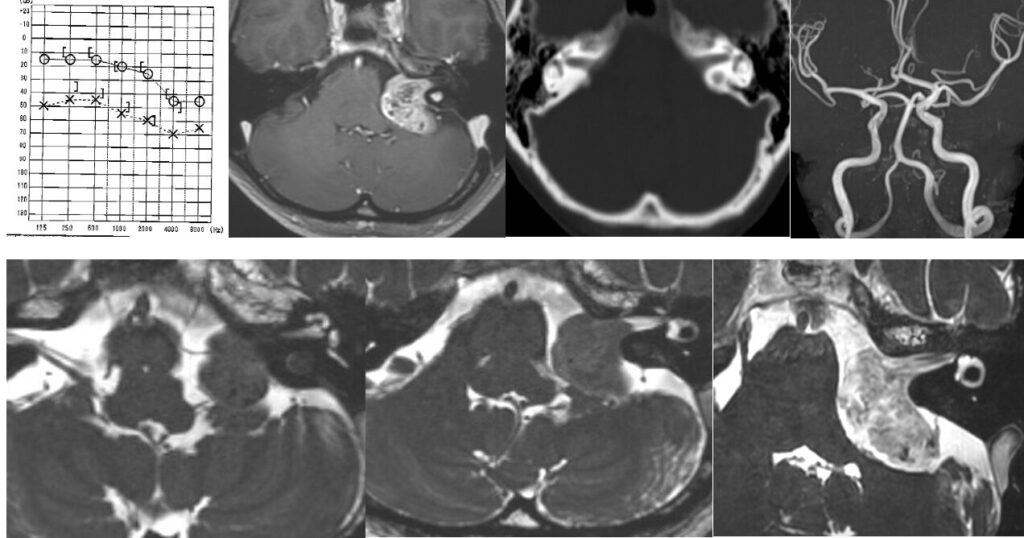

72歳男性 延髄脳幹部海綿状血管腫オペ